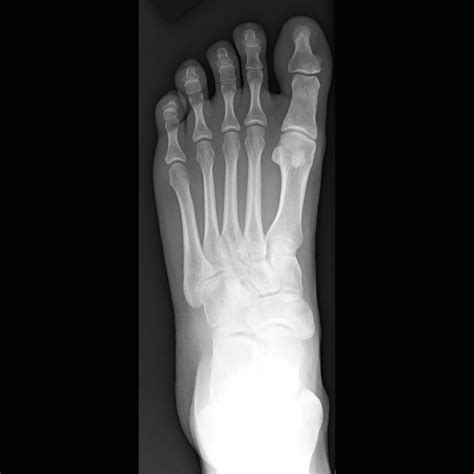

In a normal Xray, the bones should appear smooth and continuous, with no visible fractures or dislocations. The joint spaces should be uniform, and there should be no signs of bone spurs or other abnormalities.

A Normal Foot Xray typically includes several standard views to provide a comprehensive assessment. These views include:

View Description

Anteroposterior (AP) View Shows the front of the foot, including the toes, metatarsals, and tarsal bones.

Lateral View Shows the side of the foot, providing a profile view of the bones and joints.

Oblique View Shows the foot at an angle, offering a different perspective on the bones and joints.

Axial View Shows the foot from above, focusing on the metatarsals and phalanges.